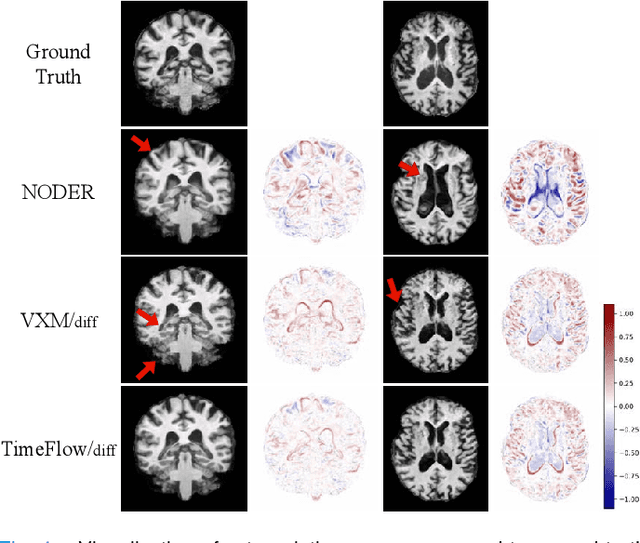

Abstract:Predicting future brain states is crucial for understanding healthy aging and neurodegenerative diseases. Longitudinal brain MRI registration, a cornerstone for such analyses, has long been limited by its inability to forecast future developments, reliance on extensive, dense longitudinal data, and the need to balance registration accuracy with temporal smoothness. In this work, we present \emph{TimeFlow}, a novel framework for longitudinal brain MRI registration that overcomes all these challenges. Leveraging a U-Net architecture with temporal conditioning inspired by diffusion models, TimeFlow enables accurate longitudinal registration and facilitates prospective analyses through future image prediction. Unlike traditional methods that depend on explicit smoothness regularizers and dense sequential data, TimeFlow achieves temporal consistency and continuity without these constraints. Experimental results highlight its superior performance in both future timepoint prediction and registration accuracy compared to state-of-the-art methods. Additionally, TimeFlow supports novel biological brain aging analyses, effectively differentiating neurodegenerative conditions from healthy aging. It eliminates the need for segmentation, thereby avoiding the challenges of non-trivial annotation and inconsistent segmentation errors. TimeFlow paves the way for accurate, data-efficient, and annotation-free prospective analyses of brain aging and chronic diseases.